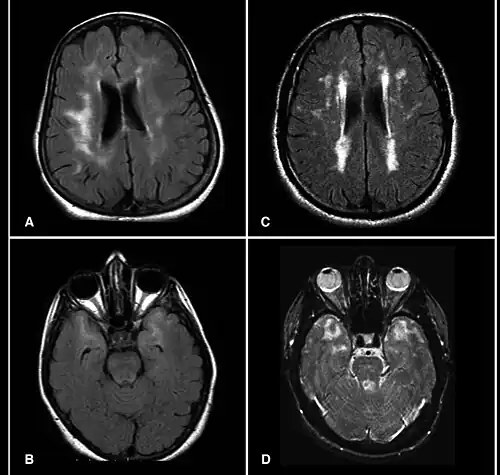

Brain MRI from patients with CADASIL showing multiple lesions.

MRIs show hypointensities on T1-weighted images and hyperintensities on T2-weighted images, usually multiple confluent white matter lesions of various sizes, are characteristic. These lesions are concentrated around the basal ganglia, peri-ventricular white matter and the pons and are similar to those seen in Binswanger disease.[2][11] These white matter lesions are also seen in asymptomatic individuals with the mutated gene.[12] While MRI is not used to diagnose CADASIL, it can show the progression of white matter changes even decades before onset of symptoms.